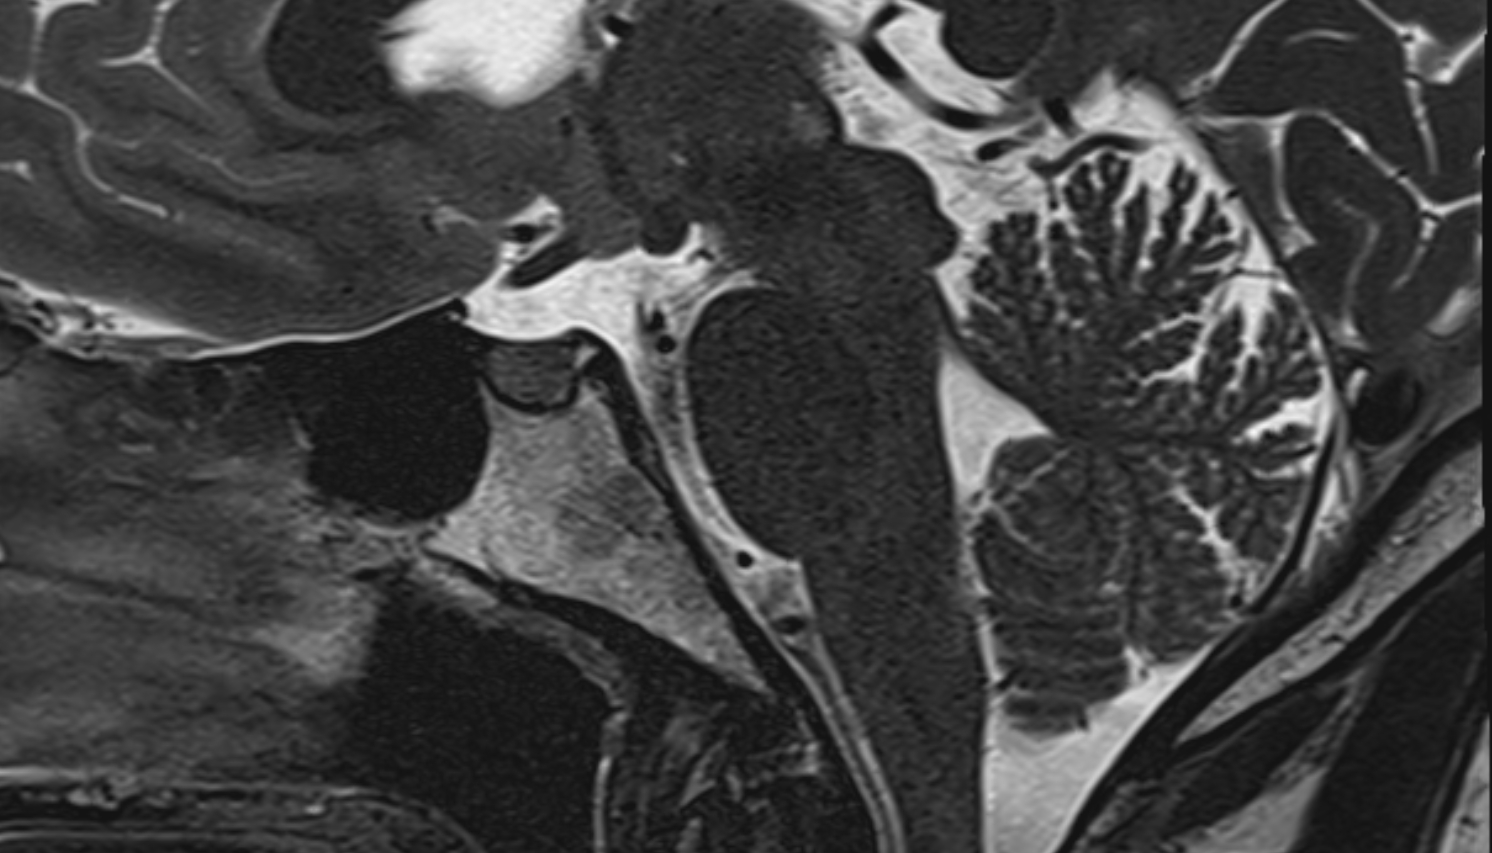

- Arbor Vitae (Cerebellar White Matter)

- Cerebellum

- Lingula of cerebellum (I)

- Central lobule (II & III) of Cerebellum

- Culmen (IV, V) of Cerebellum

- Declive (VI) of Cerebellum

- Folium (VII) of Cerebellum

- Tuber of vermis (VII)

- Pyramid of vermis (VIII)

- Uvula of vermis (IX)

- Nodule of vermis (X)

- Cerebellar tonsil (H IX)